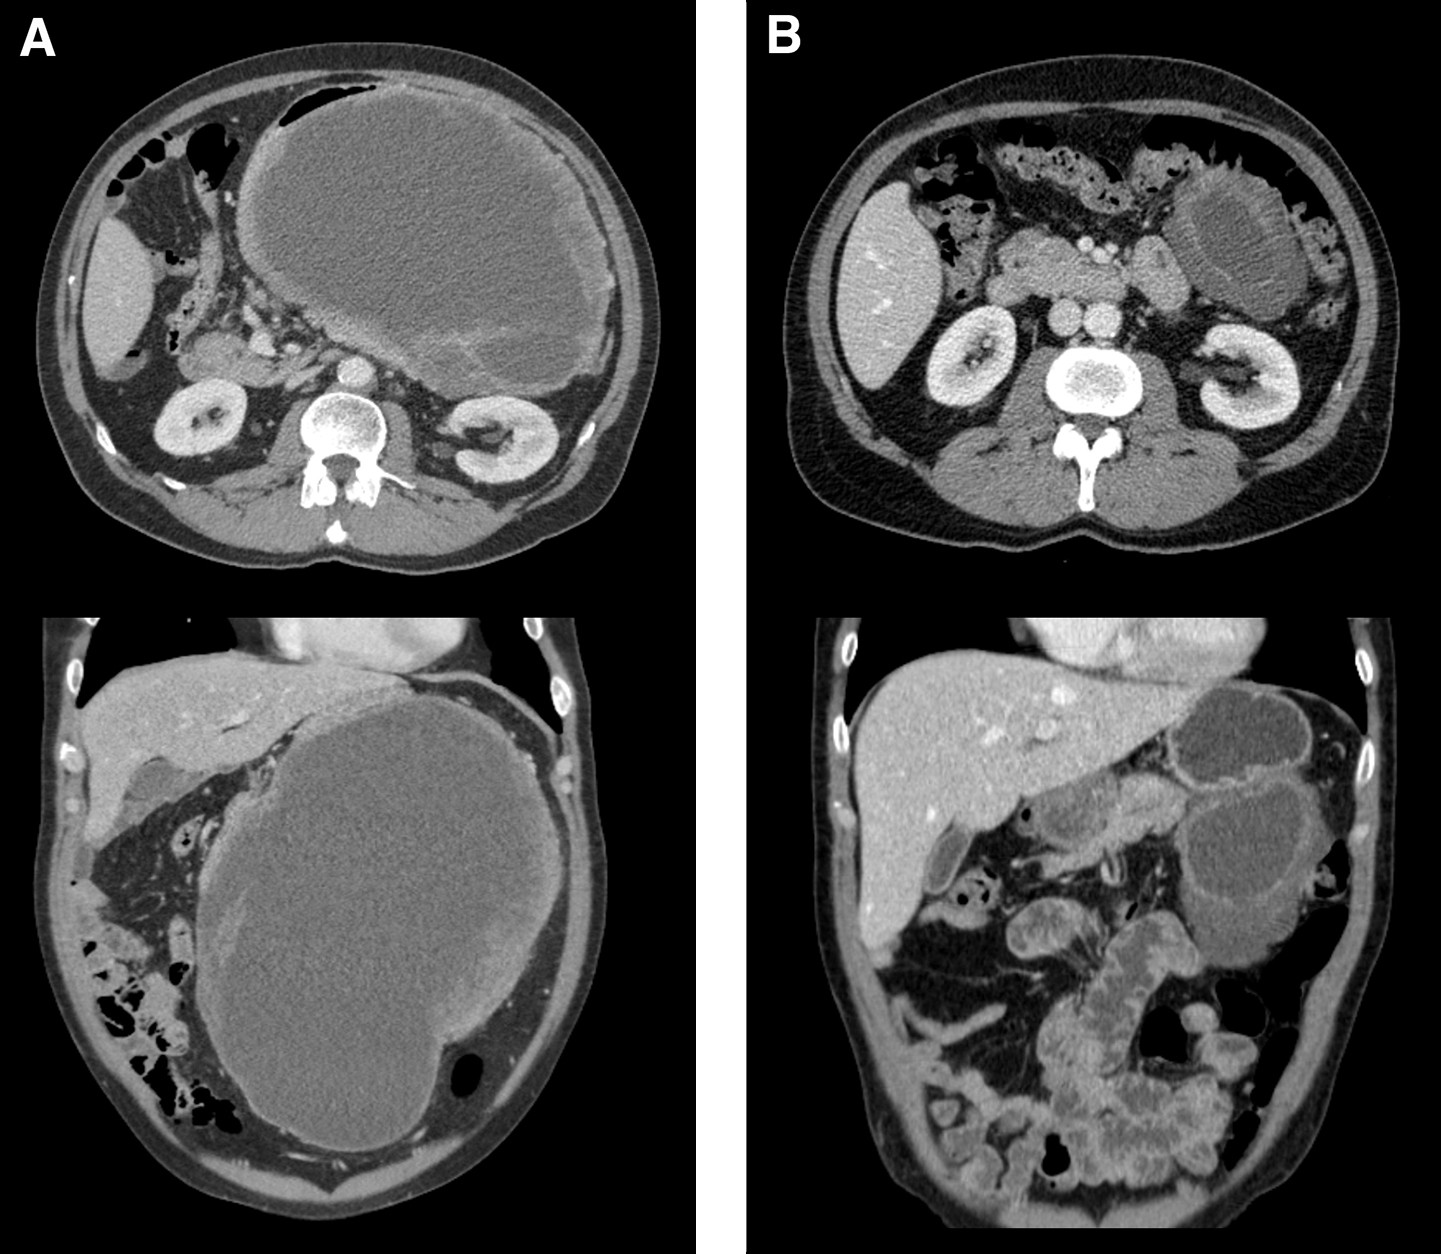

Eksisjon av tumor der man tilstreber frie marginer, er en forutsetning for helbredelse. 5- og 15-års residivfri overlevelse hos pasienter med operabel, lokalisert gastrointestinal stromal tumor er henholdsvis 70 % og 60 % (10). Gastrointestinal stromal tumor metastaserer ytterst sjelden til lymfeknuter, og det er derfor ikke nødvendig med lymfeknutedisseksjon som ved kirurgi for karsinom (7). Organbesparende kirurgi er et mål, og mange svulster kan fjernes ved lokale eksisjoner. Svulster som krever omfattende primære reseksjoner, kan ofte fjernes med lokal eksisjon etter forbehandling med imatinib i 6–12 måneder (7) (fig 3).

Radiologisk vurdering av behandlingsrespons på tyrosinkinasehemmere gjøres i hovedsak med CT (7). Primære svulster og metastaser i bukhinnen har ofte varierende grad av kontrastopptak før behandling, og ved respons ses lavere kontrastopptak og etter hvert redusert tumorstørrelse. Levermetastasene har typisk mer kontrastopptak i periferien før behandling. Ved behandlingseffekt blir de mer homogent lavtette (uttrykk for nekrose i tumor), skarpt avgrenset mot omgivende levervev og får et utseende som ligner levercyster. Respons kan initialt føre til lett økning i størrelse av levermetastaser på CT, mens størrelsen forblir nokså uendret ved vedvarende respons. For vurdering av behandlingseffekt må derfor tetthet vurderes i tillegg til størrelse (7). Diffusjonsvektet MR eller positronemisjonstomografi (PET) med 18F-fluorodeoksyglukose kan brukes til å vurdere tidlig behandlingsrespons (19) eller ved usikkerhet ved evaluering med CT. Nye metastaser, vekst av kjente metastaser eller sykdomsaktivitet i en metastase som tidligere har respondert (node in mass), regnes som sykdomsprogrediering (7).